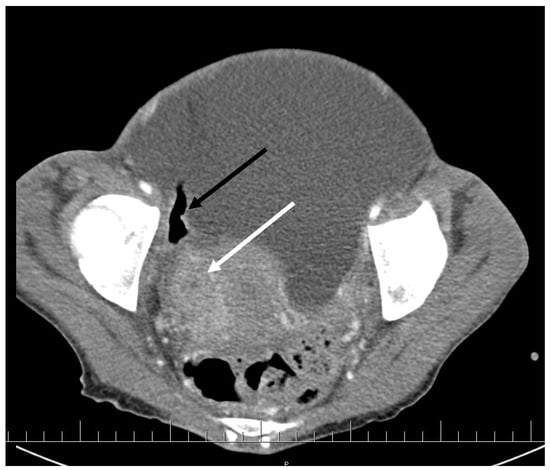

CT scan showed ascites, an enlarged right ovary with a parauterine non-homogenous mass 8 × 5 cm in size containing gas, bilateral hydronephrosis, ischaemic foci in spleen, multiple bilateral tiny nodules in the lungs with mainly subpleural distribution resembling miliary tuberculosis or multiple emboli, multiple liver lesions described as signs of Budd–Chiari’s syndrome due to the inferior vena cava thrombosis, and right hepatic vein thrombosis (Figure 1 and Figure 2).

Figure 2. Abdominal CT scan shows multiple lesions in the liver (arrows).